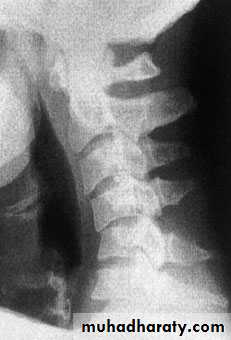

Cervical Spine X-RayLateral radiograph

A/P radiographThoracic Anatomy